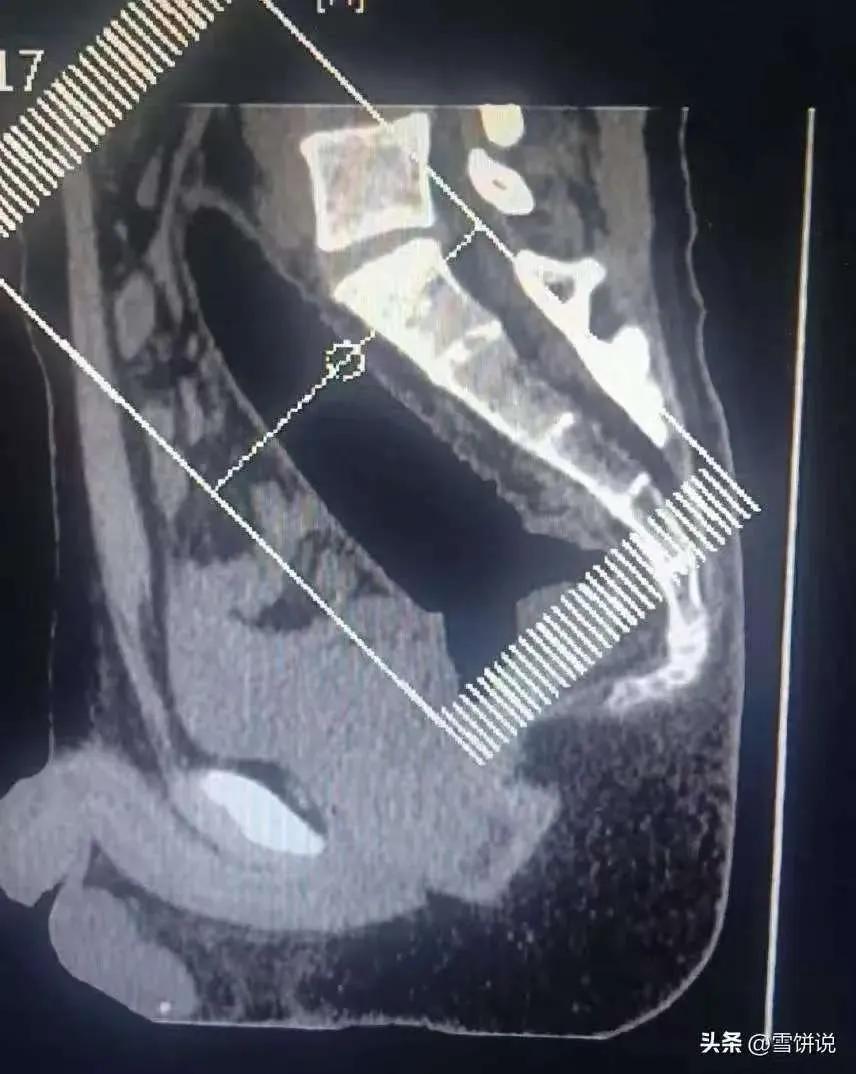

郑州icon这哥们也太敢了!捂着屁股夹着腿去肛肠科,扭扭捏捏说卡了东西,谁能想到最后取出22厘米的硅胶icon棒,医生都惊掉下巴,这哪是“狠人”,分明是拿自己身体开玩笑! 别觉得这事儿离谱,肛肠科医生见多了五花八门的异物,黄瓜、钢管、电池啥的都有。但22厘米还全钻进直肠,硅胶材质拍片子都不显影,手术风险直接拉满,肠穿孔icon、大出血可不是闹着玩的。 很多人觉得这种事尴尬就拖着,或者自己瞎折腾,反而把小问题搞大。医生说了,他们只想着救人,从不会评判患者,早就诊才是最明智的选择